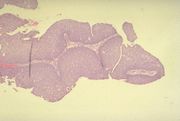

| 06:51, 23 October 2018 | Resp pap.jpg (file) |  |

53 KB | Drtbalu | |